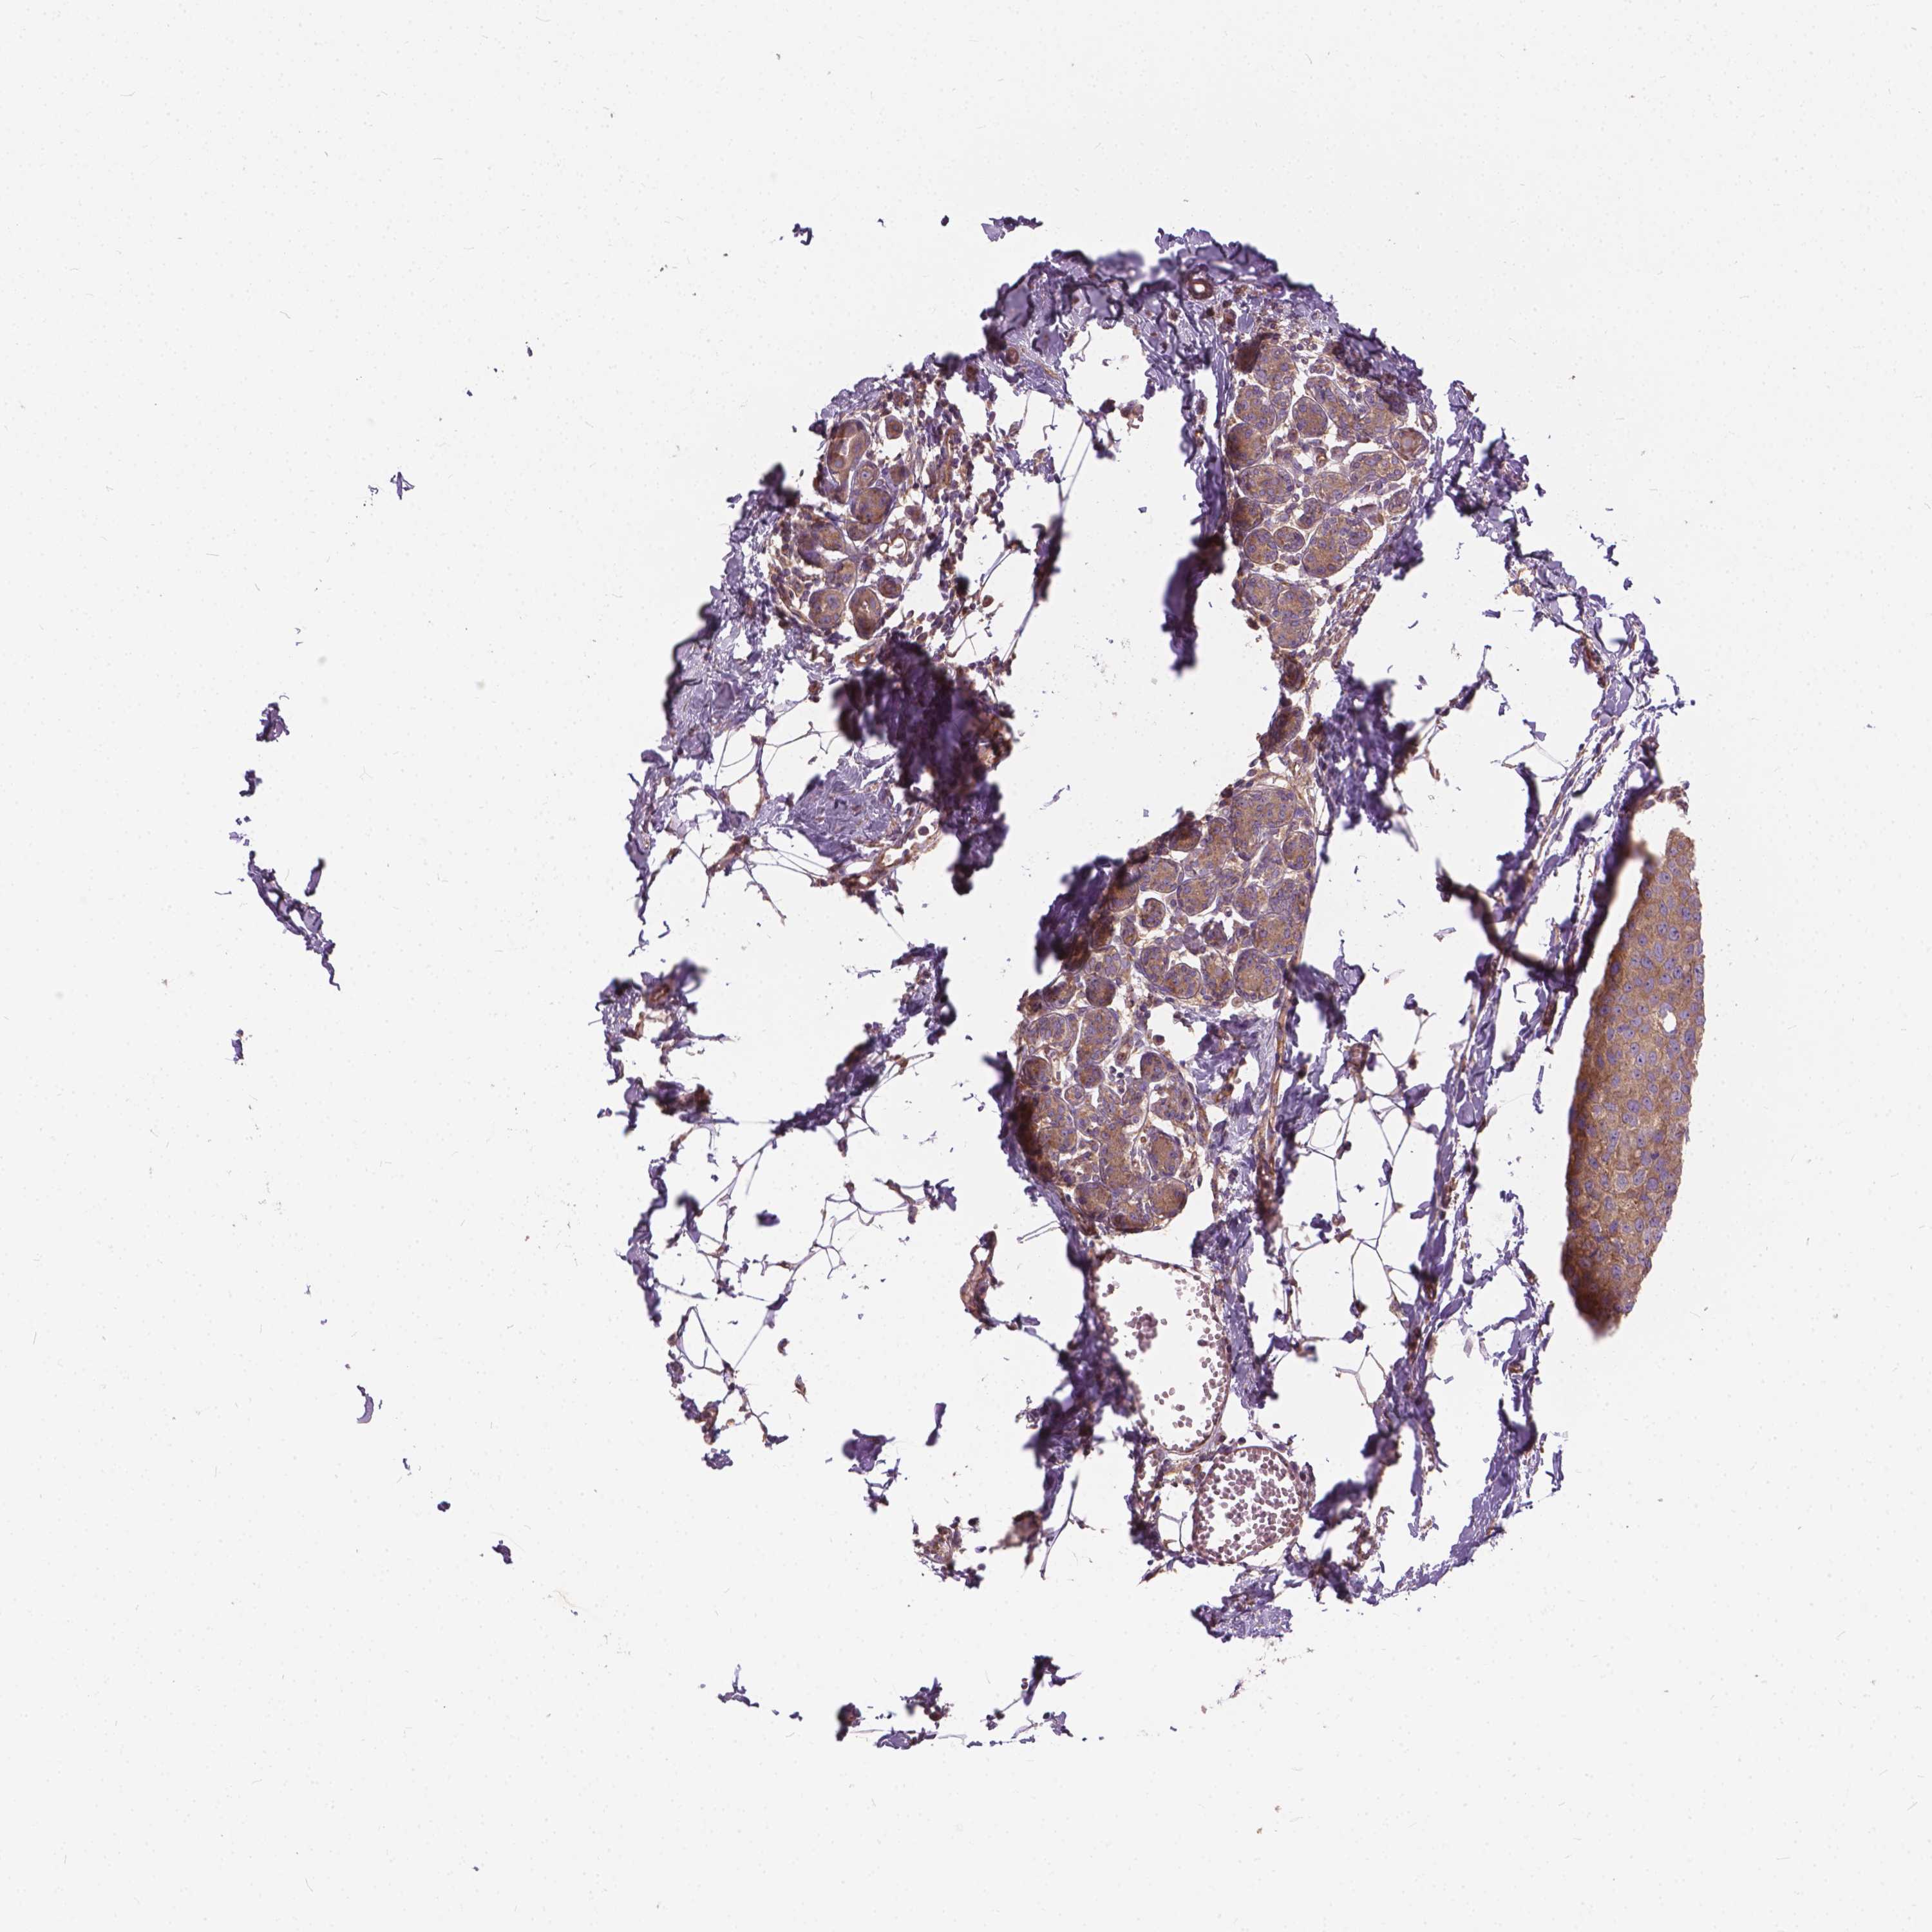

BRCA TCGA BRCA VALIDATION PROTEIN EXPRESSION

ANTIBODIES

AND

VALIDATION